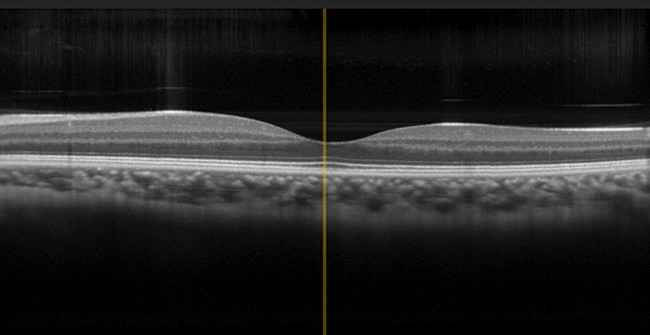

Photonic Integrated Circuits Enable High-Speed OCT Imaging of the Eye

In the U.S., eye diseases and vision problems are widespread, with diseases such as age-related macular degeneration (AMD), glaucoma, and diabetic retinopathy affecting millions of people. The NIH estimates that by 2030, 5 million Americans will have low vision, and 2.2 million will be blind, and the total economic burden for vision-related issues has been estimated to be $139 billion1. Advanced diagnostic methods aimed at early and effective identification of such diseases, including some of the most recent iterations of optical coherence tomography (OCT), hold great potential to allow for early treatment and to prevent permanent vision issues.  Read Article